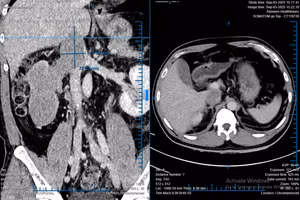

Phẫu thuật robot: Bước tiến mới trị ung thư phổi

GD&TĐ - Tại Việt Nam, ung thư phổi là nguyên nhân tử vong do ung thư cao thứ hai sau ung thư gan, với khoảng 22.500 ca tử vong mỗi năm...